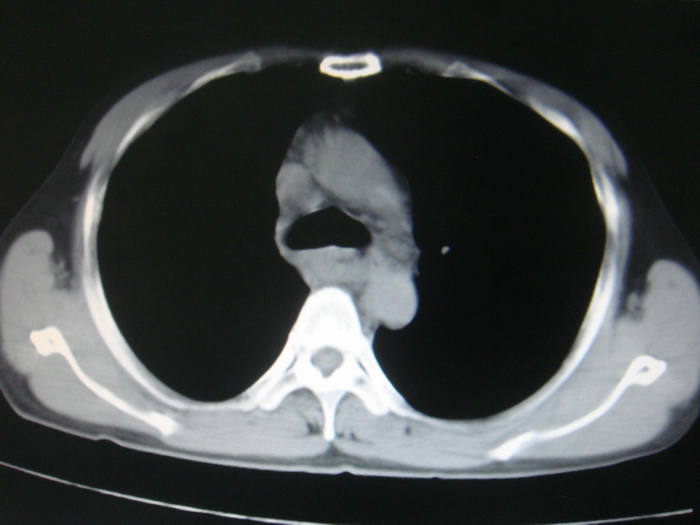

标题: CT28366:男性,45岁,偶尔发现右颈部肿块行胸部CT扫描。 [打印本页]

男性,45岁,偶尔发现右颈部肿块行胸部ct扫描。

两肺多发性转移瘤,纵隔淋巴结转移。

两肺多发性转移瘤,纵隔淋巴结转移。食道中上段管壁似乎增厚,作相关检查。

两肺多发性转移瘤,前上纵隔淋巴结转移。